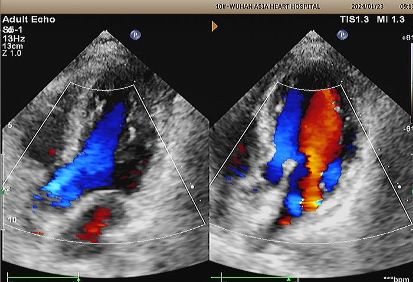

Eco de 1 ano:

No visible disc structures – replaced by 8mm tissue thickening at the septal implant site.

Zero residual shunt (rest or post-Valsalva).

Absorção completa do dispositivo confirmada.